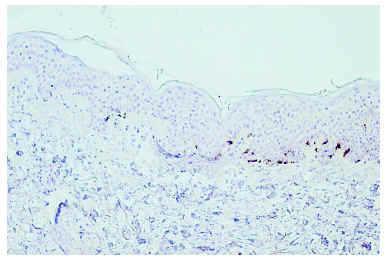

Caso 2. Varón de 28 años, diagnosticado en febrero de 2000 de un melanoma de extensión superficial en la región infraclavicular derecha, nivel III de 1,175 mm de espesor, asociado a una proliferación melanocítica benigna de apariencia congénita. Diez meses después se le realizó una linfadenectomía por una metástasis ganglionar supraclavicular derecha. Se inició tratamiento con IFN-α2b según el protocolo de Kirkwood, aunque fue necesario reducir la dosis al 50 % por la aparición de toxicidad hepática en la tercera semana. A los 5 meses de haber comenzado el tratamiento, aparecieron lesiones maculosas acrómicas asintomáticas en las regiones frontoparietales y frontotemporales. El estudio inmunohistoquímico de la biopsia de piel con Melan-A/Mart-1 mostraba una ausencia de diferenciación melanocítica en la piel afecta y la presencia de melanocitos basales en la piel sana (fig. 2). En noviembre de 2001 presentó una nueva metástasis supraclavicular derecha por lo que se le realizó disección cervical funcional y se añadió tratamiento con 6 ciclos mensuales de dacarbacina intravenosa. Terminó el tratamiento con IFN en mayo de 2002 y las lesiones cutáneas permanecieron estables. Durante el último ciclo de dacarbacina el paciente presentó metástasis cerebrales y falleció en junio de 2002, 28 meses después del diagnóstico.

Fig. 2.--Tinción con Melan A/MART-1 en la piel sana (derecha) y en la piel acrómica (izquierda). En la piel afectada existía una ausencia de diferenciación melanocítica y en la piel sana se observan los melanocitos basales.